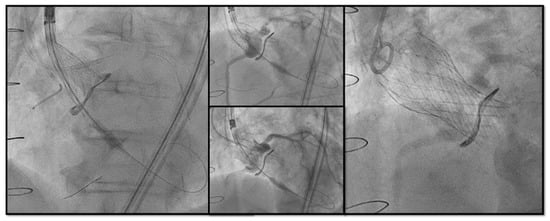

Bioprosthetic heart valves (BHV) have been increasingly implanted instead of mechanical valves in patients undergoing surgical aortic valve replacement (SAVR). Structural valve deterioration (SVD) is a common issue at follow-up and can justify the need for a reintervention. In the evolving landscape of interventional cardiology, valve-in-valve transcatheter aortic valve replacement (ViV TAVR) has emerged as a remarkable innovation to address the complex challenges of patients previously treated with SAVR and has rapidly gained prominence as a feasible technique especially in patients at high surgical risk. On the other hand, the expanding indications for TAVR in progressively younger patients with severe aortic stenosis pose the crucial question on the long-term durability of transcatheter heart valves (THVs), as patients might outlive the bioprosthetic valve.